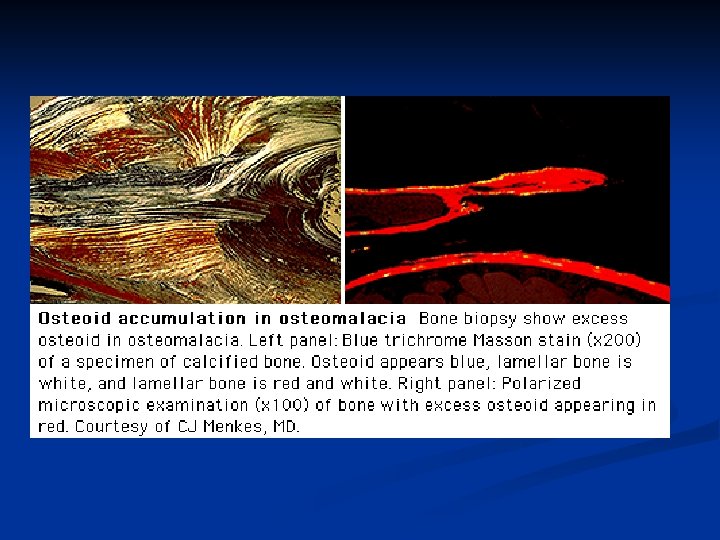

Osteomalacia & Rickets Diagnosis Bone biopsy is diagnostic n Serum 25 -hydroxycholecalciferol <50 nmol/L indicates Vitamin D deficiency n